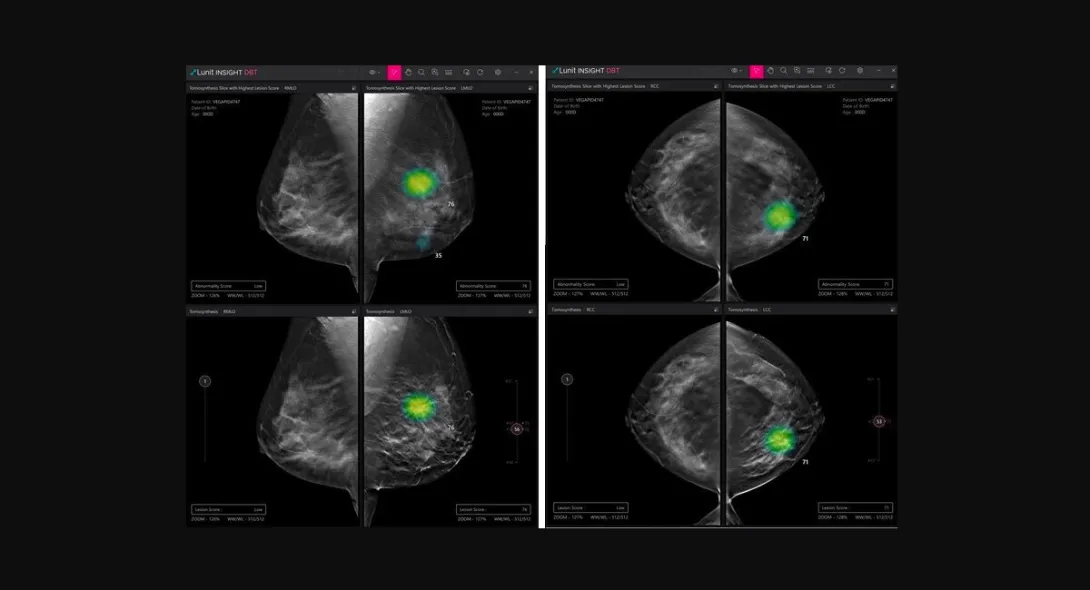

The company will introduce Lunit INSIGHT DBT which handpicks a 3D slice image with suspicious lesions among multiple images to accelerate reading and the Lunit INSIGHT Chest CT that automatically generates a detected module's location, type, volume and axial diameter.

"CT and DBT are more sophisticated examinations where you can further evaluate the specification of nodules or distinguish cancer. At this stage, our AI will be able to assist radiologists to diagnose cancer faster at higher accuracy," said Lunit Chief Product Officer Sunggyun Park.